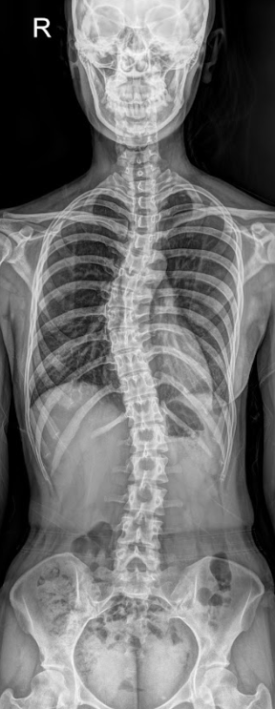

X-ray를 찍는 이유?

추체외로계 운동장애(디스토니아, 파킨슨증, 진전 등)는 주로 기저핵–뇌간 경로의 기능이상으로 발생합니다.

여기서 상부경추 변위로 뇌간에 압박이 생기면

망상체(reticular formation)

▶ 근긴장 조절 장애

전정핵(vestibular nuclei)

▶균형·자세 불안정

적핵(red nucleus)

▶ 미세운동 이상

▶ 불수의적 운동, 근긴장 이상

으로 이어질 가능성이 있습니다.

그래서 이러한 기능이상 파악을 위해 항상 X-ray로 상부경추(C0, C1, C2)의 정렬을 가장 먼저 확인합니다.

이는 정확하게 파악하고 치료하기 위함이며 상부경추(C0·C1·C2)의 회전 각도와 틀어진 방향을 수치화해

시술 전후의 변화를 비교하면 환자분이 느끼는 안정감이 실제 구조 변화와 함께 일치하는 걸 확인할 수 있기 때문이죠.

머리만 보지 않습니다.

몸 전체를 봅니다.